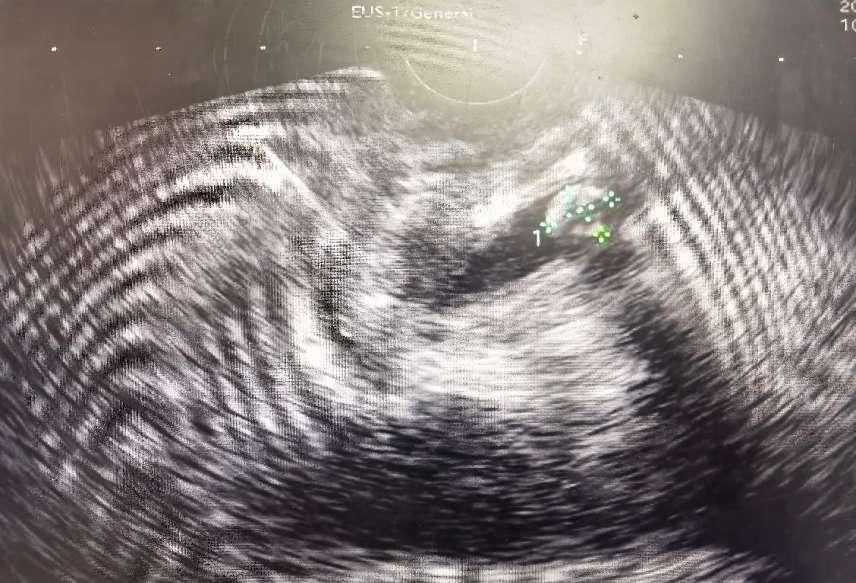

超声内镜(EUS)发现胆总管下段微小结石

超声内镜(EUS)便是破解这一难题的关键技术!超声内镜(EUS)像一名“医学侦探”精准锁定胆总管内的隐藏结石,并通过ERCP微创取石,迅速缓解危机!胆总管结石是引发腹痛、黄疸的常见病因,但有些结石“藏得深”,常规检查难以发现。